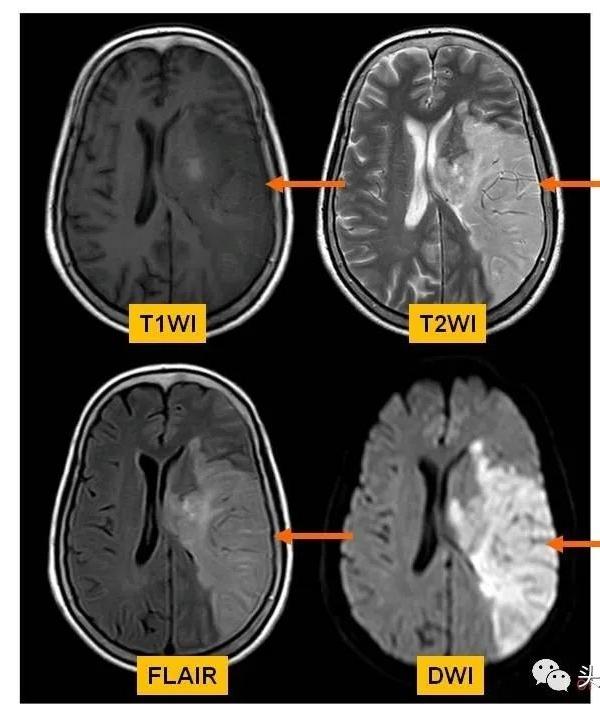

急性脑梗死头mri的临床特点「超强解读」